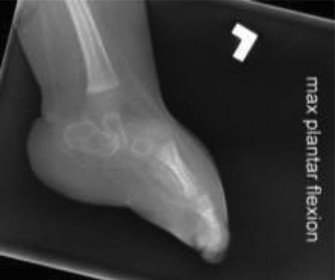

- Forced Dorsiflexion/Plantaflexion Stress Views: Lateral views with maximal forced ankle dorsiflexion and plantarflexion of the hindfoot can help assess the rigidity of the talus and the reducibility of the talonavicular joint. In true CVT, the talus remains in equinus even with forced dorsiflexion.

- Navicular Reduction onto the Talus: This is often the most challenging step. The dorsal talonavicular capsule is incised. With counterpressure on the talar head, the navicular is manually manipulated from its dorsal position onto the plantar aspect of the talar head. This usually requires significant force and persistent stretching of the surrounding soft tissues, especially the spring ligament complex, which may be elongated but still distorted. Ensure the entire talar head is seated within the navicular. This image highlights the severe dislocation and structural derangement often seen preoperatively.

- Obtain AP and lateral fluoroscopic images to confirm proper alignment of all joints and satisfactory K-wire placement. Ensure the talonavicular reduction is concentric and the talus is no longer in equinus. This image demonstrates a successfully reduced foot with K-wire fixation.